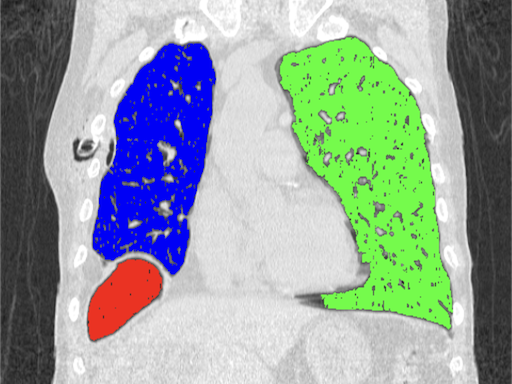

The algorithm grows regions starting from selected points based on the similarity of neighbouring pixels. It is important to properly specify a tolerance, which is the allowed percentage difference between pixels. A list of neighbours to be visited is created, then their neighbours are also added to the list, pixels already visited are removed from the list. The process continues until the list is completely empty.

# Image source: Case courtesy of Tariq Walizai, Radiopaedia.org, rID: 184833

# https://radiopaedia.org/cases/184833?lang=us

image = Image.open("path-to-resources/chest-tube.jpg").convert("RGB")

seed_points = [[135,235],

[360,215],

[115,335]] # (X,Y) coordinates of points

color_values = [(255, 0, 0),

(0, 255, 0),

(0, 0, 255)] # (R, G, B)

tolerance = 2

plt.imshow(segmented_image)

# Mark seed points

plt.plot(seed_points[0][0], seed_points[0][1], "ow", markersize=5)

plt.plot(seed_points[1][0], seed_points[1][1], "ow", markersize=5)

plt.plot(seed_points[2][0], seed_points[2][1], "ow", markersize=5)